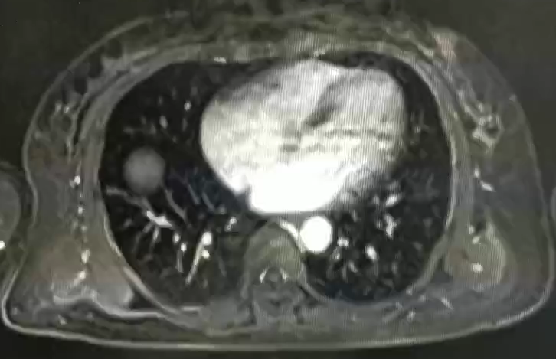

影像学检查:

栓塞后CT表现: